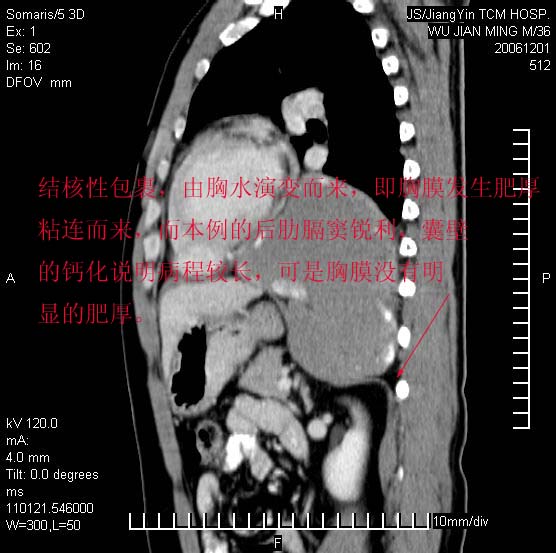

以下是引用dyqct在2006-12-1 21:17:00的发言:[br]左心缘旁及后肋膈窦区见巨大椭圆形混杂密度肿块,周围见大小不等斑片状钙化,内部无强化,周围包膜轻度强化,心脏明显受压变形,即明显占位效应,肿块广基与心包、膈相连。肝、脾内、肝门见多数小结节状钙化影。[br]考虑:1、左心缘旁及后肋膈窦区慢性包裹性胸膜炎(结核性);[br] 2、肝、脾及肝门淋巴结核已钙化。[br]

以下是引用zrs在2006-12-2 17:28:00的发言:[br]肺内、肝脾内虽有钙化,但不支持结核性胸胸膜炎包裹,而支持寄生虫感染![br][br]

以下是引用zyx168在2006-12-2 10:10:00的发言:[br][br]肝脾肺内多发钙化灶